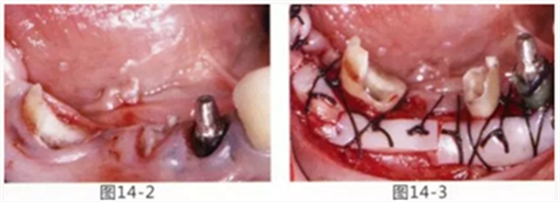

病例5

為了提高對(duì)修復(fù)體的術(shù)后效果,以生物學(xué)寬度,獲取附著齦為目的進(jìn)行游離齦移植的病例

圖14-1 修復(fù)體周圍角化牙齦較少,很難進(jìn)行清潔的狀態(tài),并有緣下齲壞的發(fā)生。

圖14-2,3 徹底去除齲壞后,試圖通過(guò)游離齦移植獲取生物學(xué)寬度和附著齦。

圖14-4~6修復(fù)體周圍角化牙齦較少,很難進(jìn)行清潔的狀態(tài),并有緣下齲壞的發(fā)生。

圖14-7 配戴最終修復(fù)體完成5年后的狀態(tài)。保持良好。